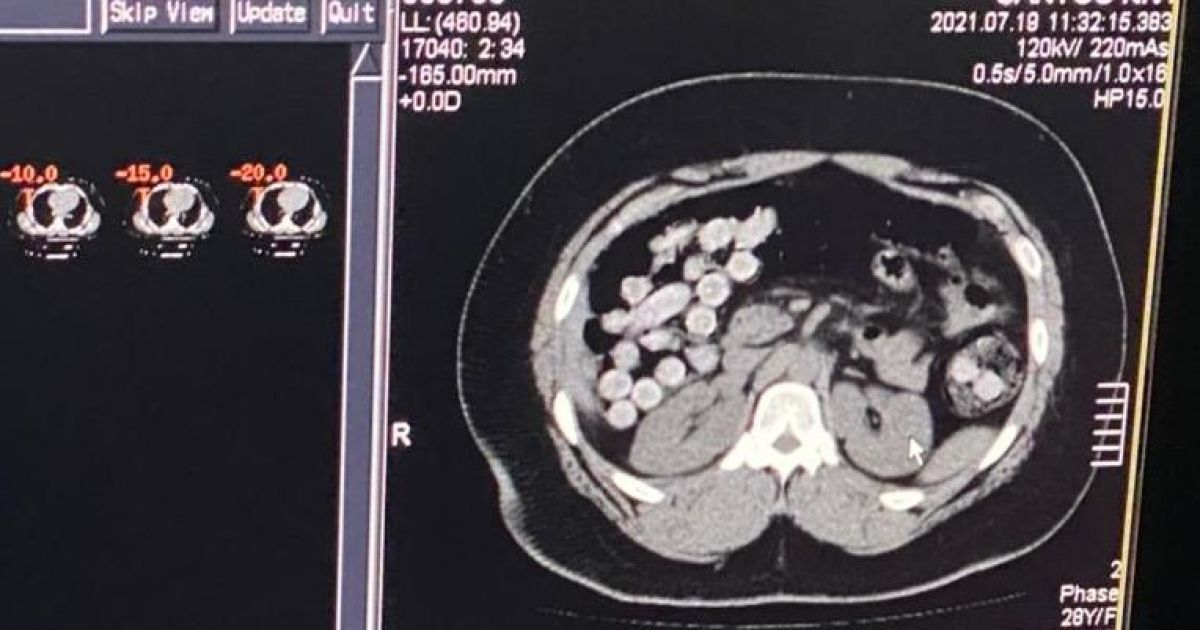

В международном аэропорту "Борисполь" разоблачили мужчин, которые завозили в Украину кокаин из одной из стран Латинской Америки. Один из задержанных пытался перевезти через границу более 1 кг кокаина в желудочно-кишечном тракте.

Всего правоохранители обнаружили 2 кг кокаина. Один из злоумышленников перевозил наркотики в личных вещах. Еще 1 кг кокаина обнаружили в желудочно-кишечном тракте другого злоумышленника. Таким образом он пытался перевезти наркотик через границу.